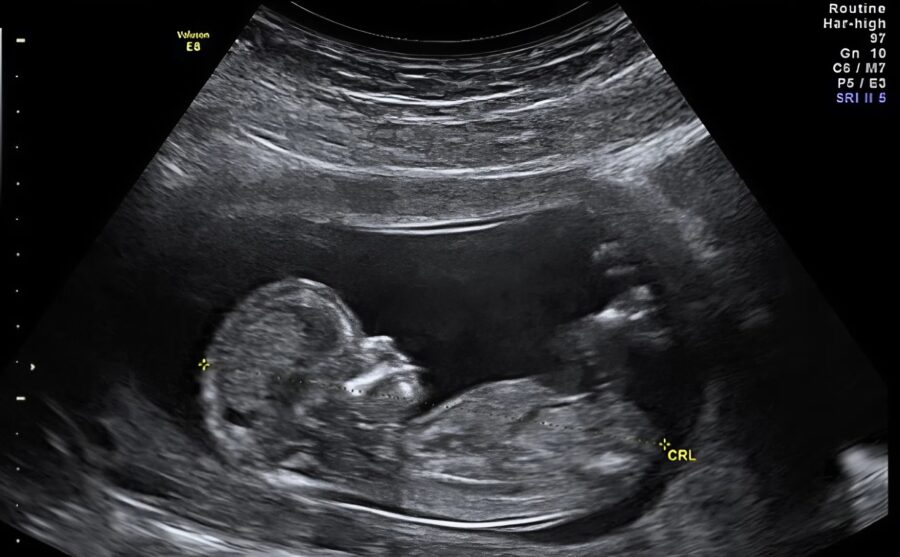

During my last prenatal exam, the doctor displayed behavior that deeply unsettled me. I went to the consultation thinking everything was fine, expecting just a routine check-up before the baby’s birth. But, when he saw the ultrasound, his attitude unexpectedly changed.

When he looked at the ultrasound, a clear sense of worry appeared on his face. I asked if everything was okay, and he answered in a low, almost hesitant voice: “Go home, stay away from your husband.” Then, he suggested I live with my sister and think about getting a divorce.

Seeing my confusion, he slowly turned the ultrasound screen towards me to explain what was troubling him so much. What he showed me and what he revealed was much more concerning than I had imagined.

The ultrasound showed signs of a rare but serious infection.

He told me that the disease he suspected could be transmitted through intimate contact, and that my husband might be carrying a virus or bacteria that was particularly hard to detect.

According to him, this kind of infection could have consequences for my health and the baby’s health.